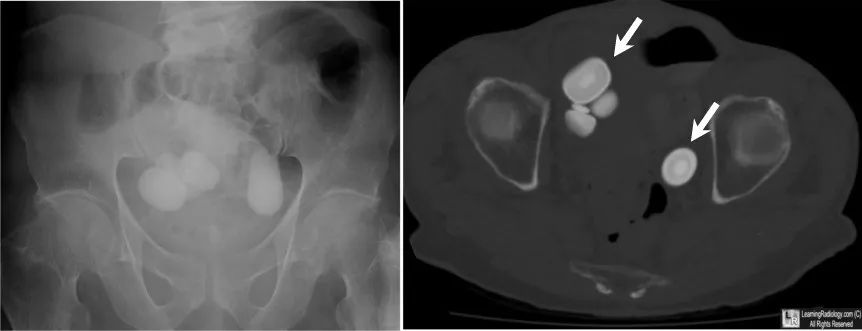

图3 膀胱结石。左图常规X光片,显示膀胱内几处非常大的椭圆形钙化灶。右图CT扫描骨窗,再次显示膀胱内多处大的层状钙化(白色箭头)